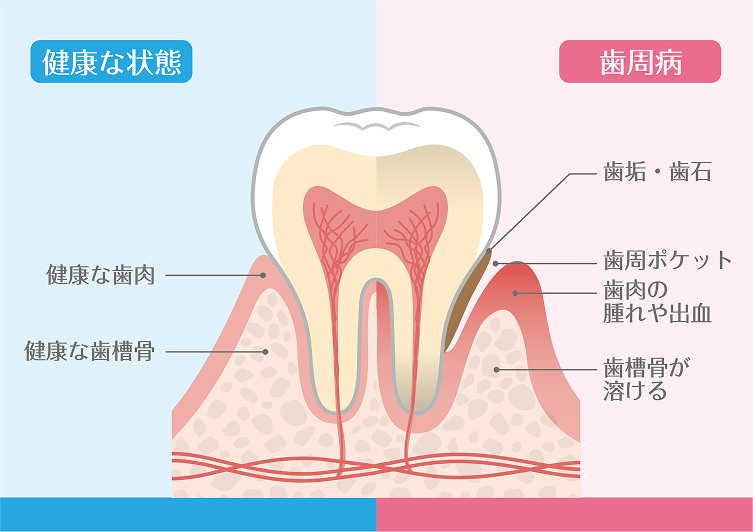

歯周病は初期段階では痛みがほとんどないため見過ごされがちですが、放置すると歯を支える骨が溶け、最終的には歯を失うリスクがあります。

歯石除去(スケーリング)

歯と歯茎の間に溜まった歯石を特殊な器具で除去します。歯肉炎の主な治療法として効果的で、出血や炎症の改善につながります

歯の根元のお掃除(ルートプレーニング)

歯周ポケット内部の歯根表面を清掃し、細菌の再付着を防止します。歯周炎の治療に必要な処置です。